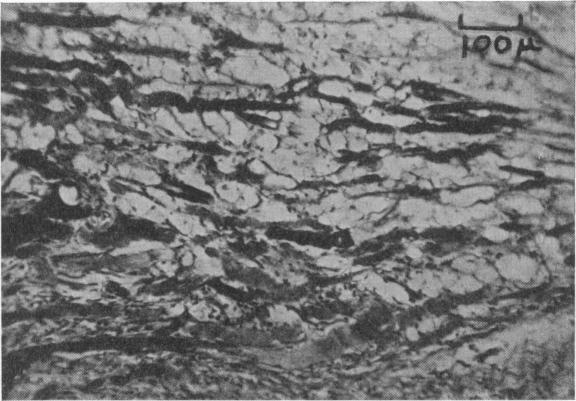

Invasion of nerve homografts by regenerating muscle fibres.

J Anat. 1950 Oct;84(4):394.